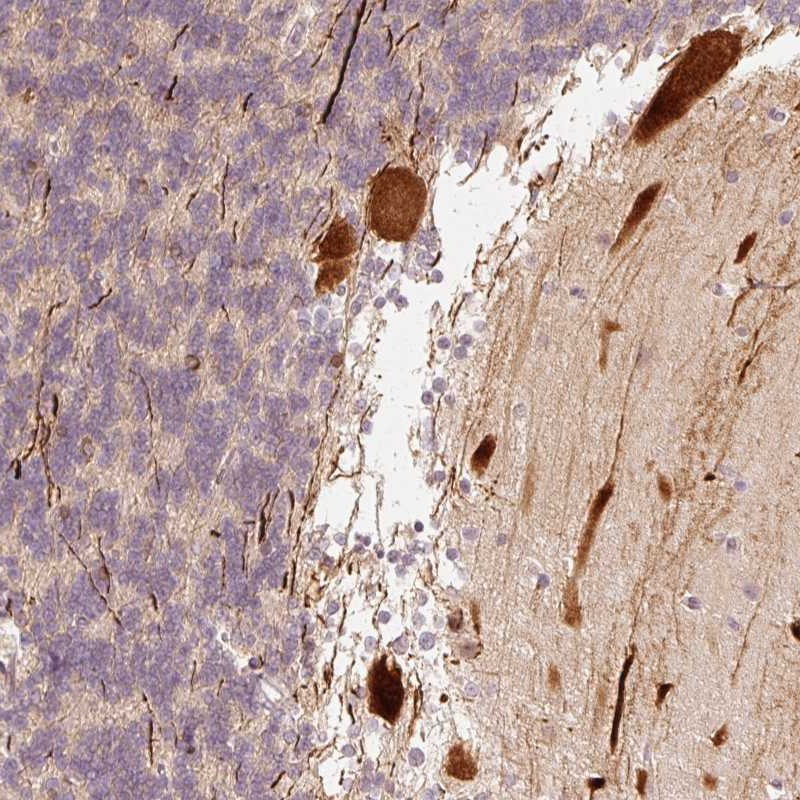

Immunohistochemical staining of human cerebellum shows strong cytoplasmic and nuclear positivity in Purkinje cells.